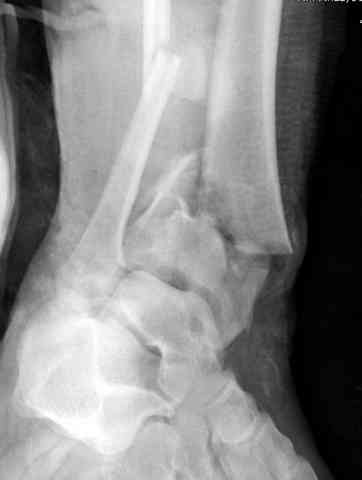

Дополнительные ренгенограммы после дистракции и

обязательная комьютерная томография дают возможности разузнать топографию расположения фрагментов, что немаловажно для планирования хирургического доступа.

По апексу фрагмента ориентируется при планировании

фиксации, также предоперационно определяется

направление фиксирующего материала: шурупа или спицы с упорной площадкой.

Здесь выставлена пара случаев перелома пилона, оба

случая леченные этапным наружным фиксатором.